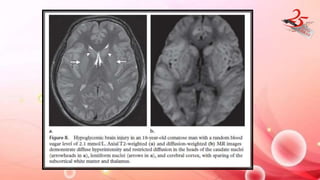

HYPOGLYCEMIA

• CLINICAL FEATURES : Diabetic pts, Seizures , focal neurological

deficits and coma.

• Extent of brain damage depends on severity and duration of

hypoglycemia.

IMAGING FINDINGS:

• T2 hyperintensity in cerebral cortex , hippocampi and BG

• Mild reversible hypoglycemia – transient and isolated WMI with

true diff restriction involving splenium , internal capsule and corona

radiata.

• BG INVOLVEMENT : POOR PX